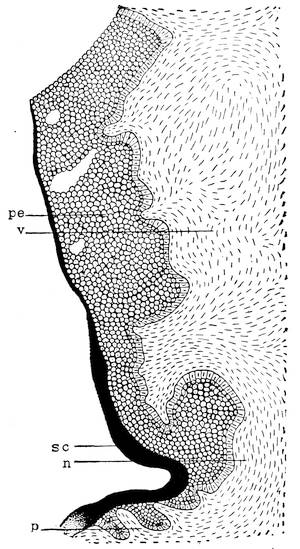

The genital tubercle ceases to grow in the female and becomes the clitoris. The genital folds or the lips of the vestibule become prolonged and form the labia minora or the nymphae. The genital swelling increases in size through adipose and fibrous tissue. The part situated on the ventral side of the clitoris becomes the mons veneris, while the lateral parts are converted into the labia majora of the vulva.

The scrotum being a derivative of the abdominal wall, it follows that its wall will consist of the same elements as the abdominal wall. The first layer of the abdominal wall, the epi30dermis or cutis, forms also the epidermis of the scrotum. The fascia superficialis abdominis constitutes the second layer of the scrotum, or the tunica dartos. The musculus obliquus abdominis externus goes to make up the third layer, the so-called Cooper’s fascia. The musculus obliquus abdominis internus forms the fourth layer, or the musculus cremaster externus. The musculus transversalis abdominis furnishes the cremaster internus muscle, and the tunica vaginalis communis, or the fifth layer. Finally, the double layer of the abdominal peritoneum forms the tunica vaginalis propria of the scrotum. Between the two lamina of this tunica is found some fluid which, when pathologically increased, constitutes the anomaly called hydrocele.